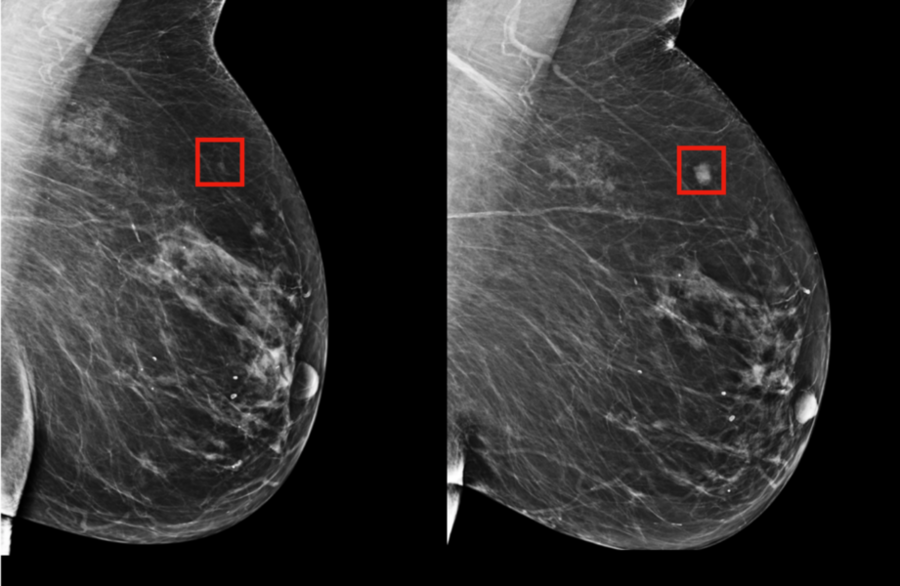

We have all seen the incredible images of early breast cancer detection done by MIT researchers. Their work in cancer treatment and prevention has already been backed up by studies, which is incredibly exciting for the industry. Yet, policymakers are worried such application of AI and machine learning could be imposing on patient’s personal data, which could be used against them or for profit by enterprises who try to sell prescriptions and medications, medical equipment and procedures.

Source: MIT